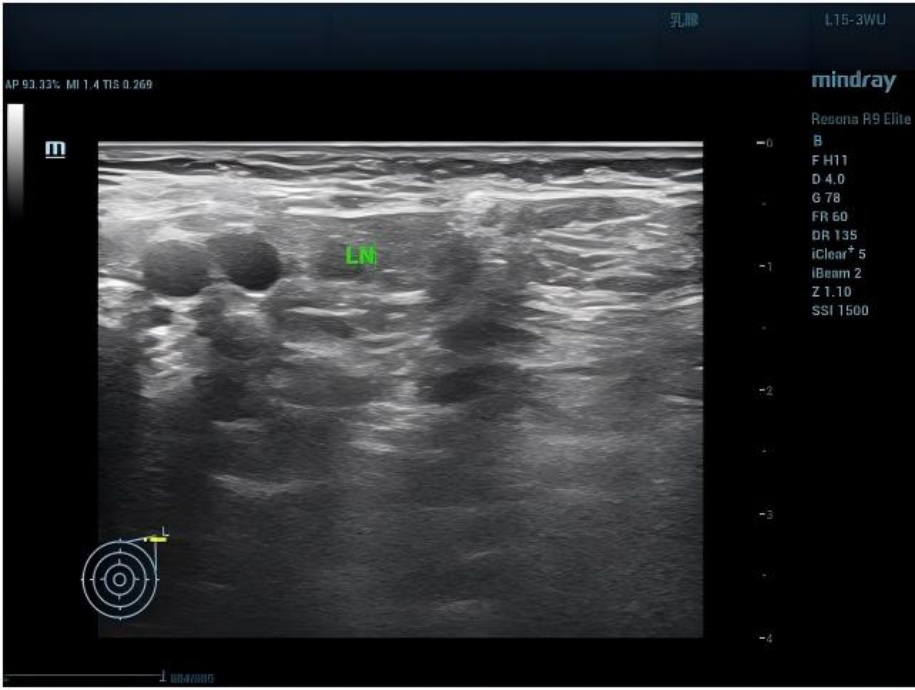

泌尿系超声(2025-05-20):左肾轻度积水(集合系统分离22 mm);右肾重度积水(集合系统分离98 mm),皮质变薄(厚约2.3 mm),结构不清。膀胱未见异常(见图2)。

Figure 2. Ultrasound of the right kidney showing significant dilation of the renal pelvis and calyces, presenting as anechoic areas, suggesting hydronephrosis

2. 右肾超声示:肾盂肾盏扩张明显,呈无回声区,提示肾积水